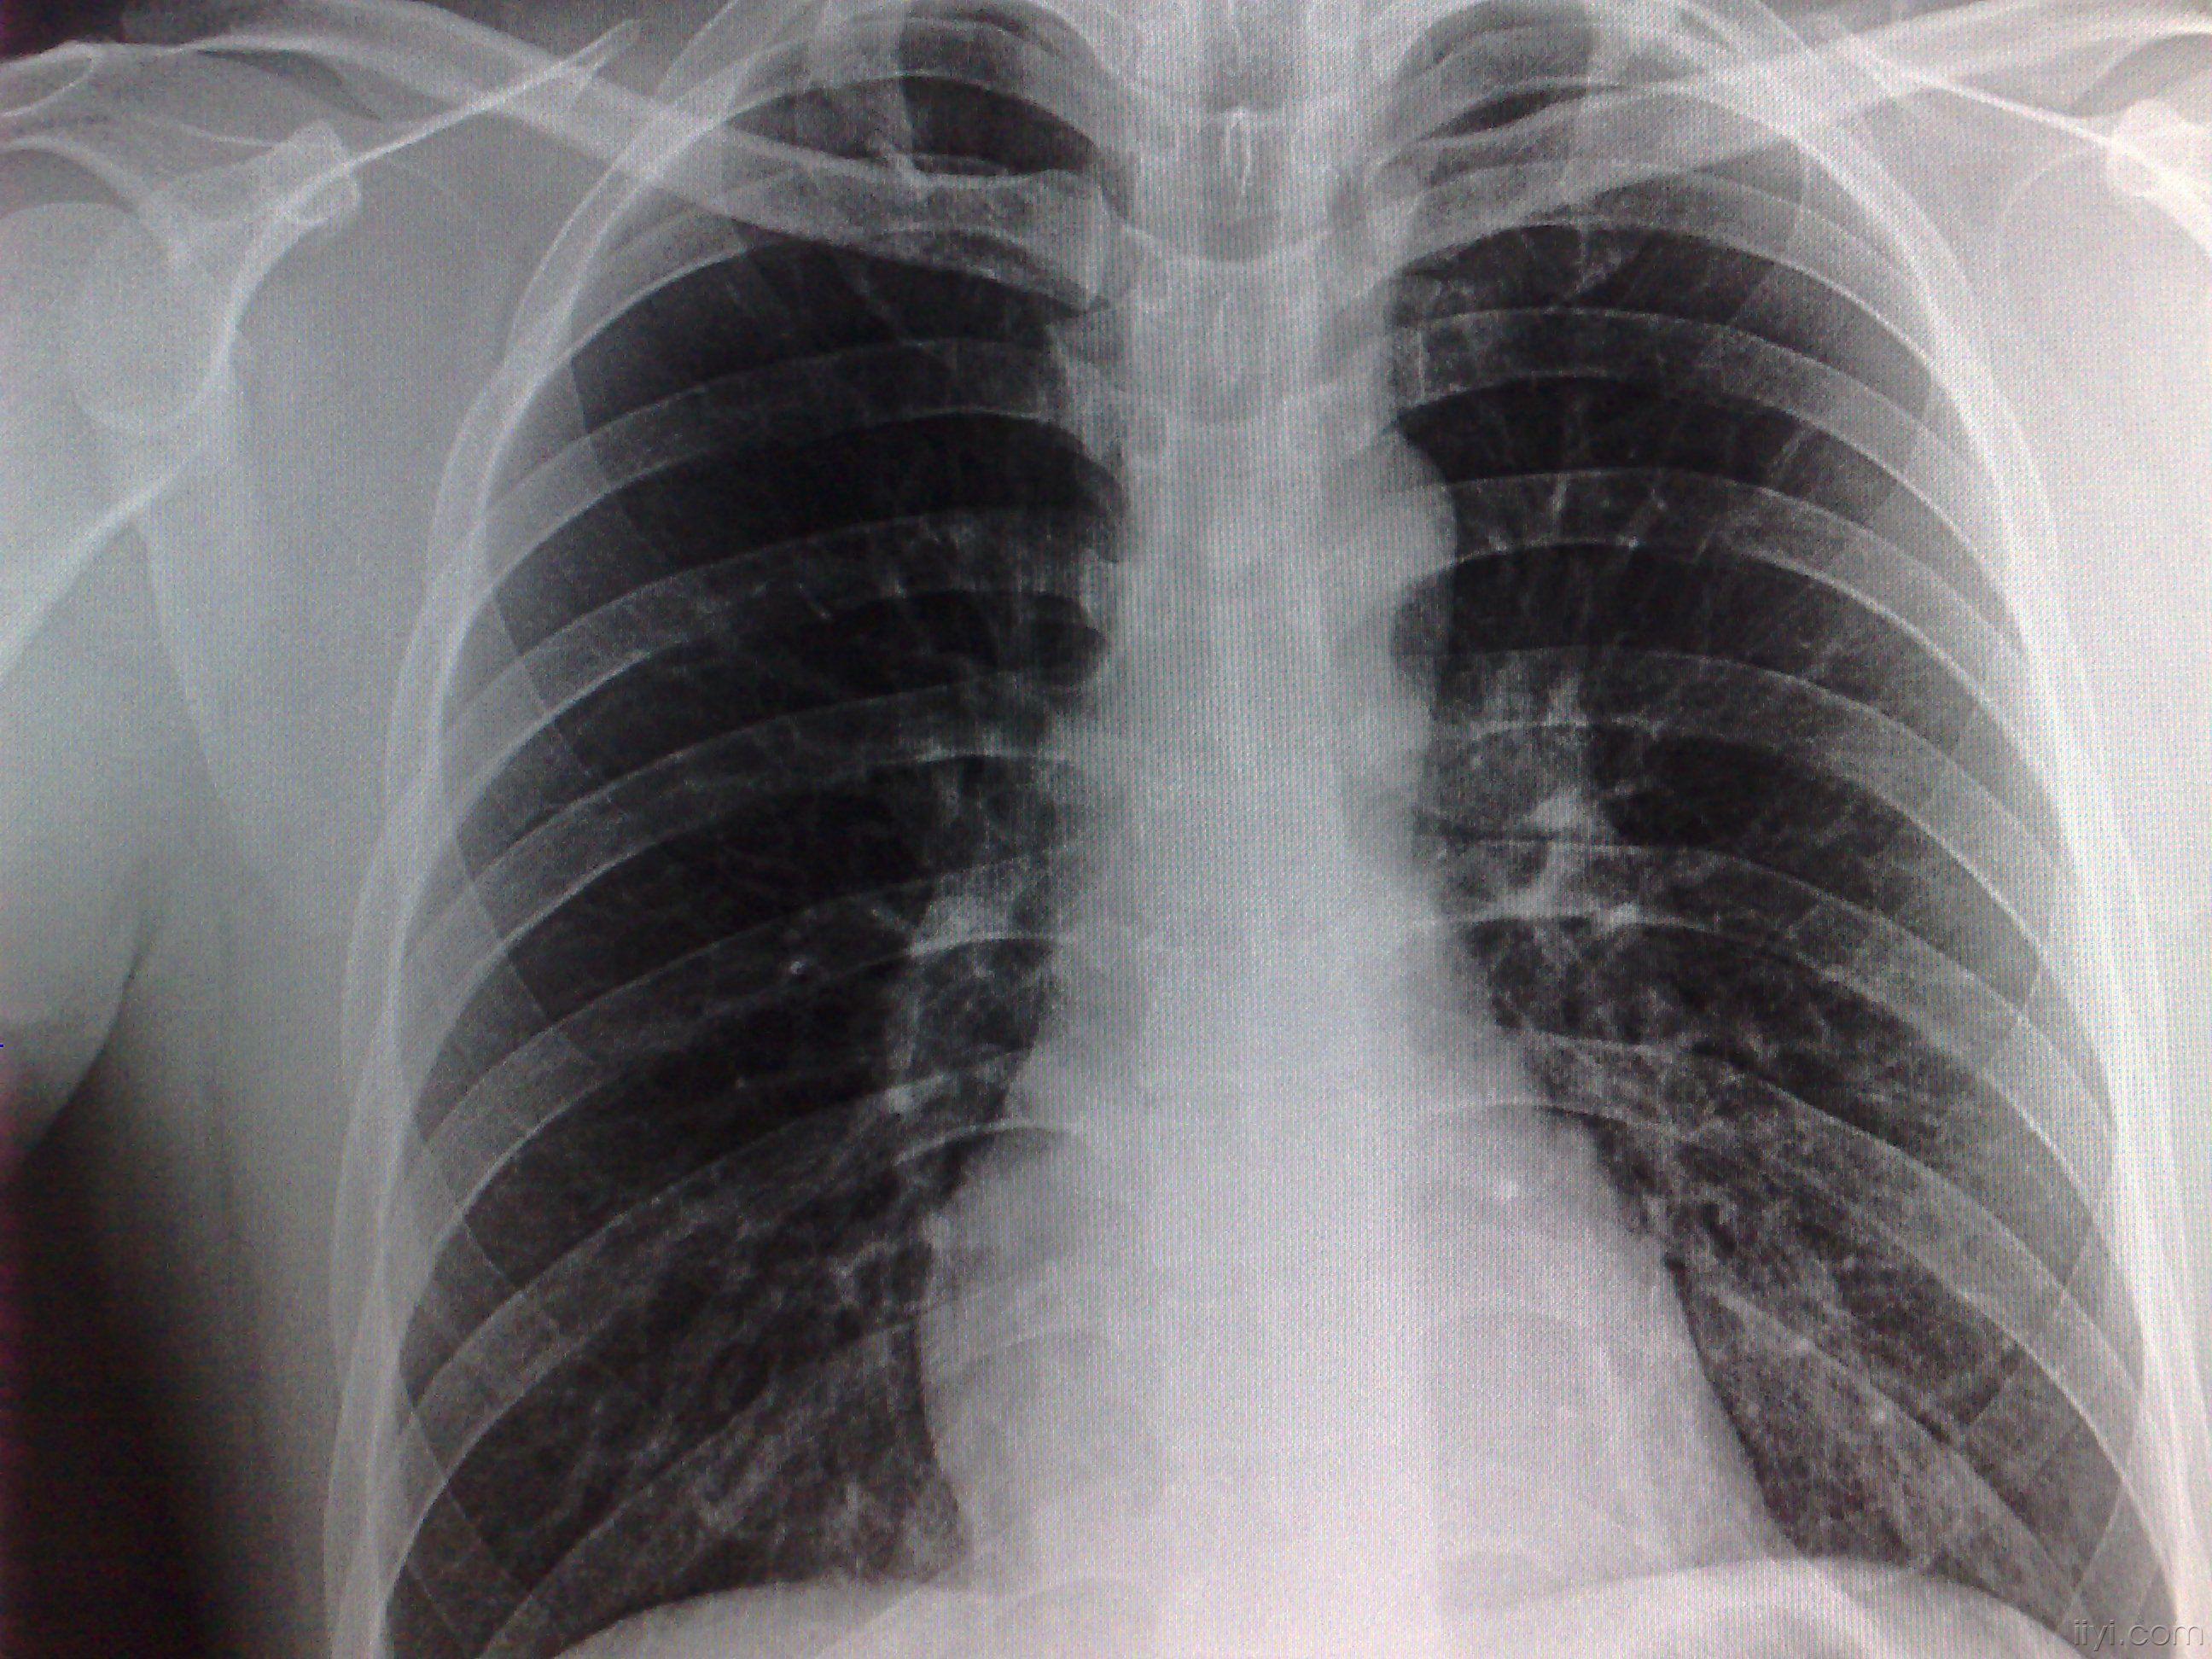

去医院拍了个片说肺部纹理增粗增大说是支气管炎 但感觉他没仔细看 麻烦有懂这个的帮看看有没有阴影之内的

大家看一下这胸片是什么问题